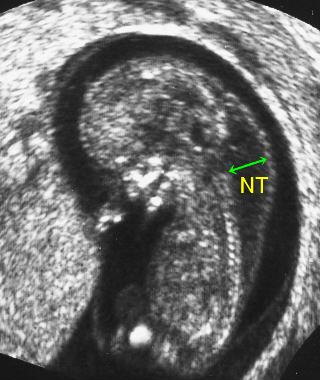

Nt

02 妊娠初期 胎児の頸部浮腫 Nt 妊娠11 13週でcheck 深谷産婦人科 医学情報

胎児の首の後ろのむくみ 浮腫 Nt とは 妊娠初期 All About

Nt Nuchal Translucency について 出生前検査 Nipt 遺伝カウンセリング 妊婦健診 エコー検査 産科 婦人科 産婦人科

胎児の首の後ろのむくみ 浮腫 Nt とは 妊娠初期 All About

胎児の首の後ろのむくみ 浮腫 Nt とは 妊娠初期 All About

胎児の首のむくみ Nt クリフム夫律子マタニティクリニック